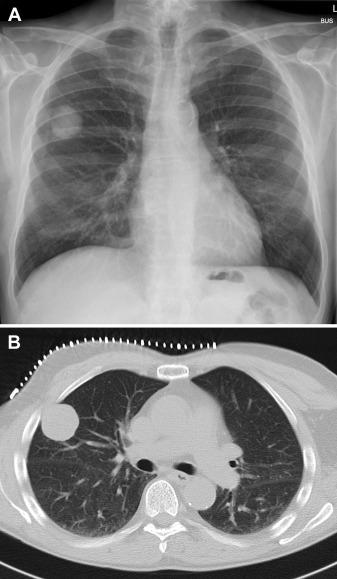

入院时ECG和肌钙蛋白水平正常,认为不太可能发生急性心脏疾病。实验室检查结果血红蛋白11.7 g/dL(参考值:14-18)和γ-谷氨酰转移酶566 U/L(参考值 ≤60),所有其他数值均在正常范围内,包括电解质、肝酶、肌酐、尿素、C-反应蛋白、WBC计数和血小板。胸片示右肺肿块边界清晰(图1A)。胸部CT(图1B)在邻近胸膜的右肺上叶出现低密度圆形结节,直径为3.4 cm。行CT引导下活检,活检组织细菌培养和细菌16S核糖体RNA聚合酶链反应(PCR)及4周后的真菌培养均为阴性。组织病理学结果见图2。

图1 A.胸片中右肺肿块边界清晰;B. 胸部CT显示,右肺上叶临近胸膜出现低密度圆形肿块(直径3.4cm)